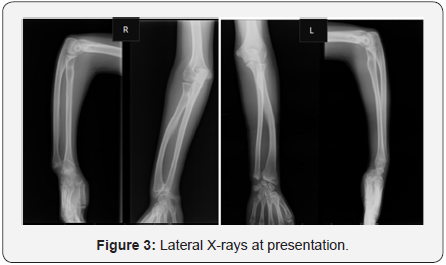

The postero anterior wrist X-rays (Figure 2) showed typical Madelung deformity changes on both wrists: shortening of the radius compared to the ulna, radially curved radius, a mismatch of the distal radioulnar joint and a triangular-shaped carpus. The lateral projection (Figure 3) demonstrated predominant changes on the right wrist: dorsal dislocation of the ulnar and an exaggerated volar tilt of the radioulnar joint in a way that made palmar carpal displacement and an anterior translation of the hand and the wrist. It was performed on the right side ametaphysic triplane osteotomy of the distal radius with Vicker’s ligament release, and an ulnar shortening osteotomy with plate fixation (Figure 4). There was no intra and postoperative complications.